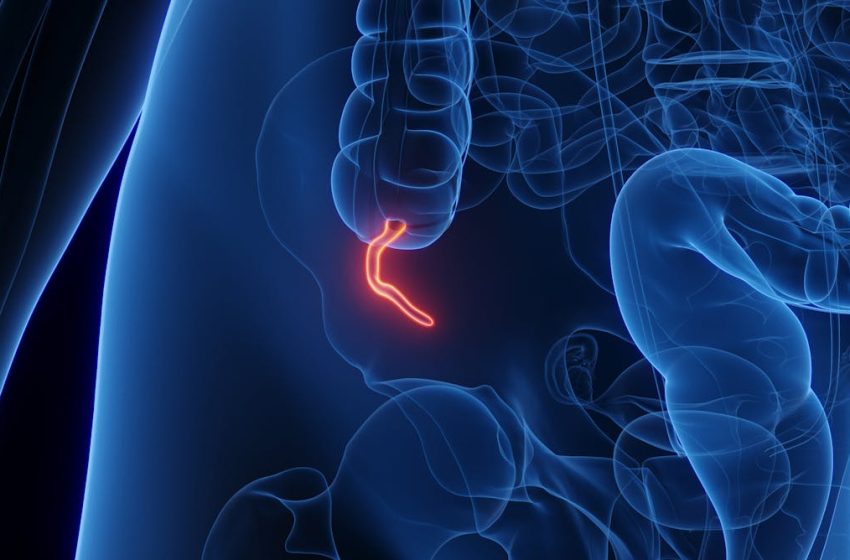

The appendix is a small pouch branching off the first section of the large intestine. Its shape and structure vary widely across species – a clue that evolution may have tinkered with it more than once.